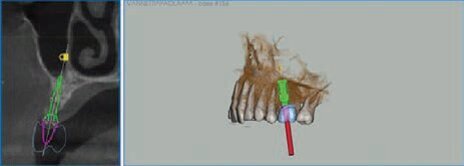

La pianificazione software della fase chirurgica e l’utilizzo di una guida per il corretto posizionamento dell’impianto “asse implantoprotesico”, (Fig. 2) ci permettono non solo di ottenere il posizionamento implantare nel rispetto dello spessore osseo disponibile “asse anatomico” ma anche di ricercare la migliore soluzione protesica avvitata, “asse protesico”, per una sensibile riduzione del rischio di errore. Interessante inoltre notare come con l’ausilio del software per progettazione implantoprotesica e utilizzando la riproduzione virtuale della ceratura diagnostica sia possibile allineare l’asse implantare all’elemento protesico in modo ottimale, utilizzando come riferimento il prolungamento dell’asse dell’impianto e facendolo emergere nella posizione ottimale al centro della corona protesica. In assenza di informazioni protesiche, come spesso succede, la posizione implantare suggerita dall’anatomia ossea non coincide poi con la posizione ideale per la protesi.

Fig. 2 - Differenza tra asse anatomico proposto dalla protesi e asse protesico necessario per ottenere un’estetica del manufatto protesico.